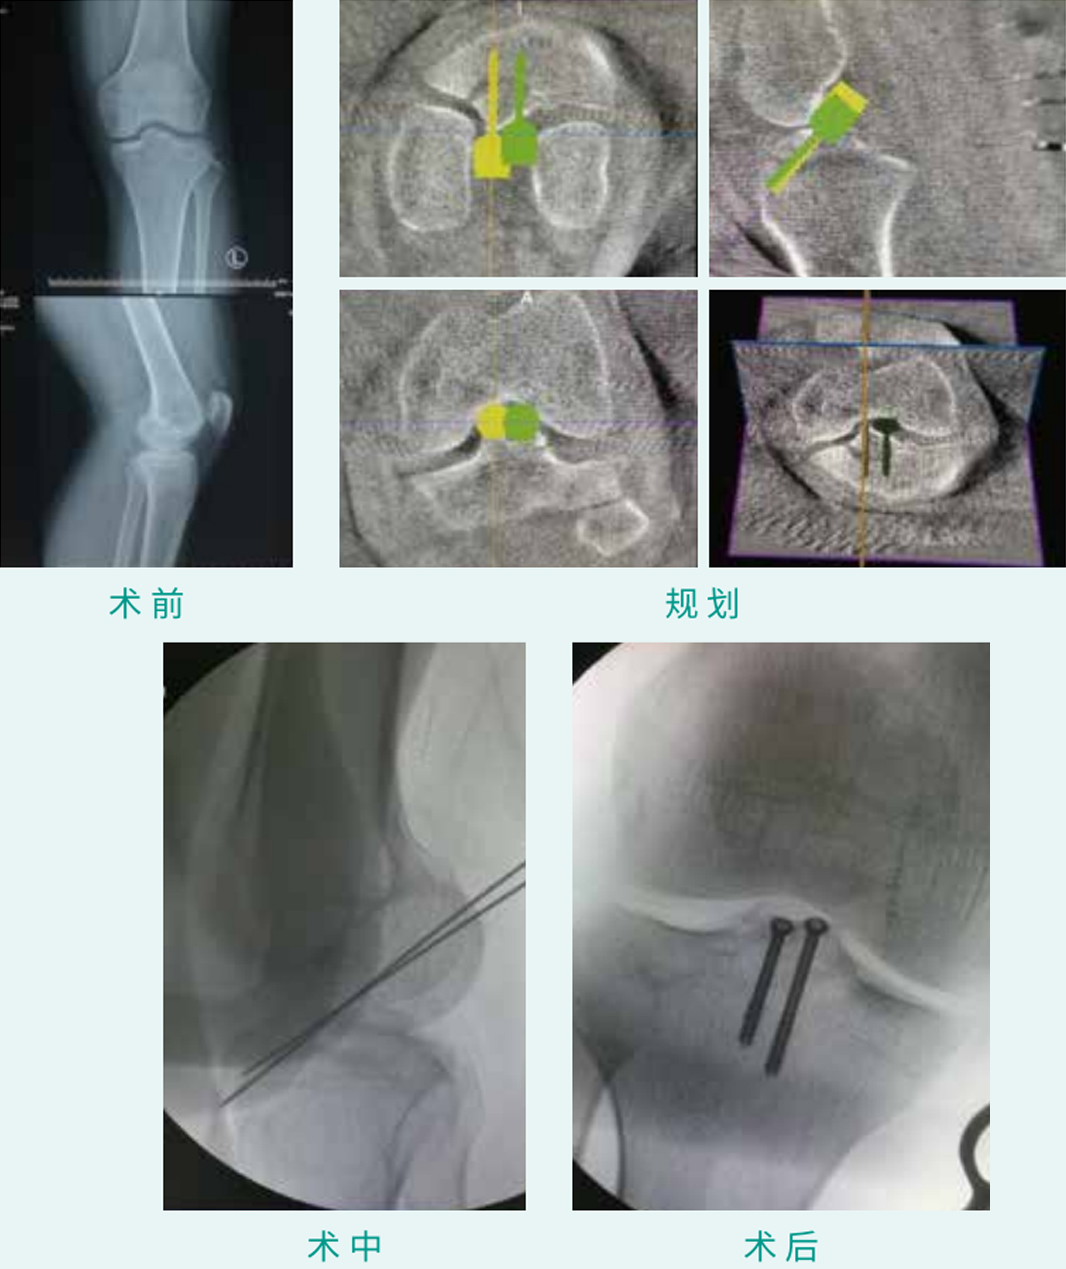

TiRobot ? Intercondylar Eminence Percutaneous Screw Fixation

天玑? 辅助髁间嵴经皮空心螺钉内牢靠术

基本情形:患者男,,,,,,,26岁,,,,,,,胫骨髁间嵴撕脱骨折

机械人累积用时:15分钟

植入物:2枚空心螺钉

病例泉源:烟台山医院 姜传强